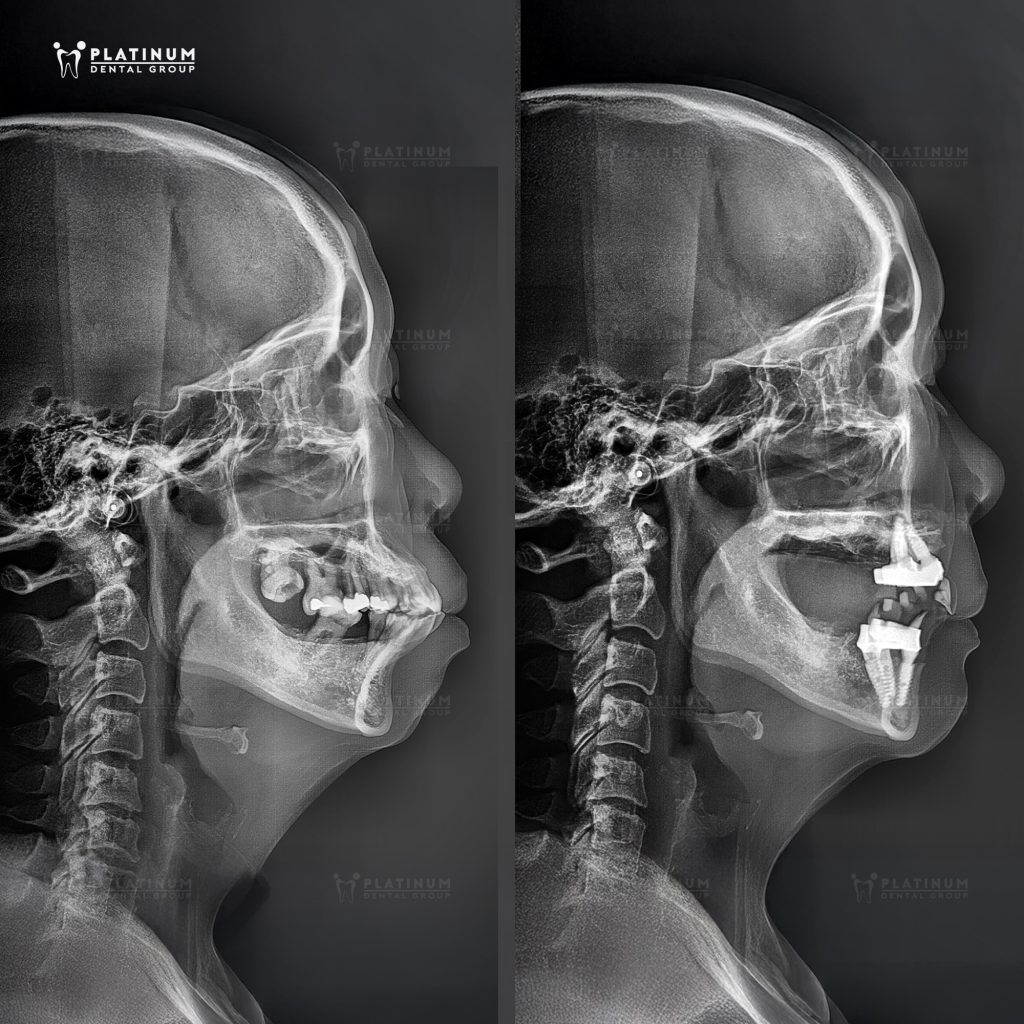

Sau khi đánh giá tổng thể tình trạng răng – xương – khớp cắn, bác sĩ Dương Minh Tùng đã xây dựng kế hoạch trồng răng Implant All-on-4 cho cả hai hàm, tính toán kỹ lưỡng hướng cắm trụ và phục hình trên nền hô xương, đưa trục răng và khớp cắn về vị trí phù hợp. Sự tính toán này trở nên chính xác hơn khi kết hợp cùng hệ thống định vị động trong cấy ghép Implant, vừa phục hồi khả năng ăn nhai toàn hàm, vừa điều chỉnh lại nền hàm hô, hướng đến khớp cắn hài hòa.